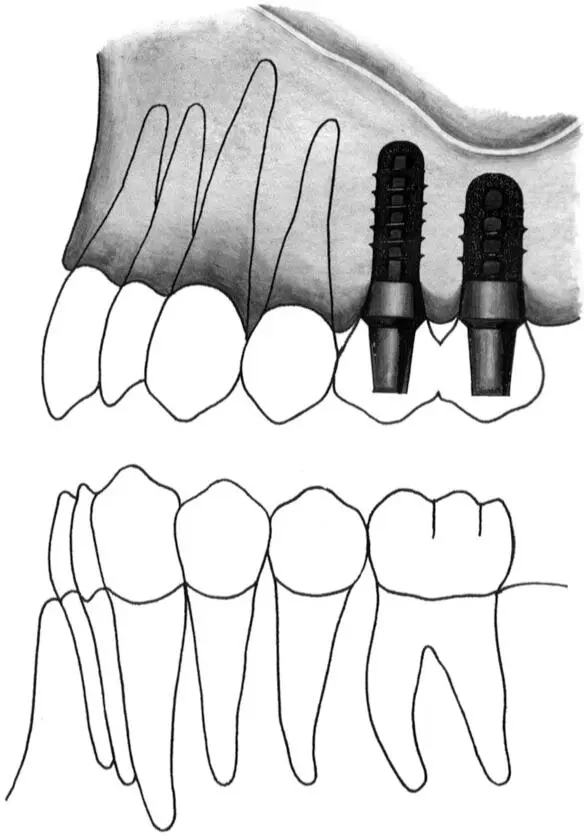

Figs 1-11g and 1-11h Occlusal (g) and lateral (h) views of regular neck and wide neck implants. When a regular neck implant and a wide neck implant are indicated to replace a missing second premolar and molar, the regular neck implant should be placed 4 to 5 mm from the tooth and the wide neck implant placed approximately 9 mm from the anterior implant.